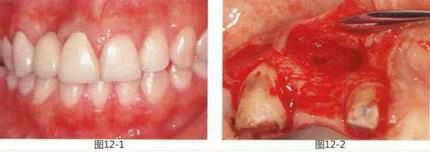

圖14-1  Seibert分類Class 3.術前。

圖14-2  將臨時修復體的橋體部形態(tài)進行調整,使其達到滿意的形態(tài),并確認缺失部牙槽嵴空間。

圖14-3  將多功能蠟覆蓋在缺失部上,來推測所需移植瓣的量。

圖14-4  從口內拿出的臨時橋體和多功能蠟。